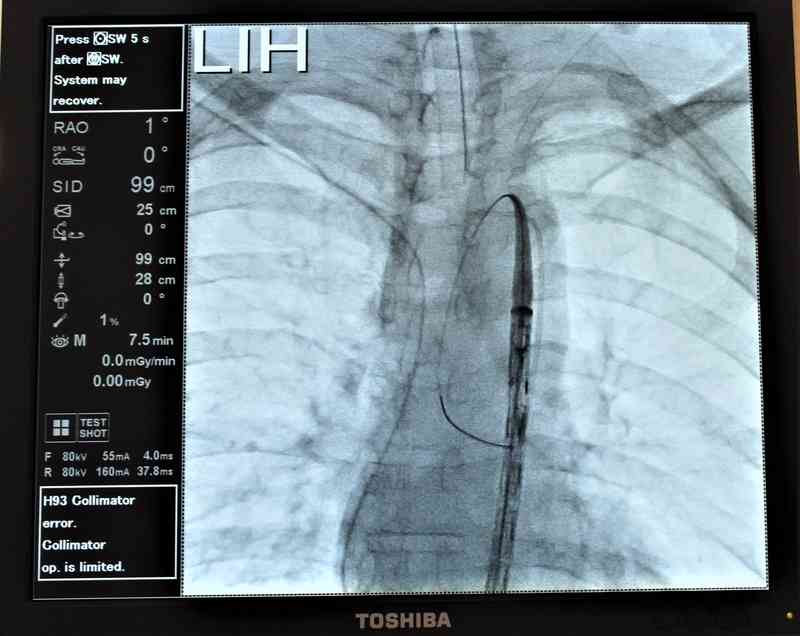

Що було зроблено? Відновлення цілісності судини, закріплення стенту, адже розрив аорти стався в місці, яка живить ліву руку. Тепер ліву руку буде живити ендопротез, який було імплантовано пацієнту. Це перший етап операції. Сучасний судинний протез, який утримує форму, вкритий вуглецевим покриттям, яке на досить тривалий час забезпечить своє нормальне функціонування. За словами столичного фахівця, квінтесенцією нашого візиту є етап встановлення між ушкодженими ділянками судини ендопротезу, який заводиться через стегнову артерію всередину аорти і сам розправляється. Він фіксується до неушкодженої ділянки перед місцем розриву, та до неушкодженої ділянки після місця розриву.

Оперативне втручання такого рівня раніше для Вінниці було нереальним, а сьогодні стало можливим. Саме забезпечення сучасним устаткуванням Вінницької обласної клінічної лікарні ім. М. Пирогова, робота на новому ангіографі надала можливість фахівцям надати допомогу пацієнту тут і зараз. Для цього не потрібно транспортувати хворого в Київ, особливо як у даному випадку.

«Не дивлячись на політравму, наше хірургічне втручання стало для хворого мініінвазивним, – підкреслив Ігор Дітківський, заввідділу ендоваскулярної хірургії ІССХ ім. М. Амосова НАМН України. – Ми зробили два доступи по 4 см на шкірі, ніяких розрізів тканин, чи кісток – тобто вони є максимально ощадними і практично непомітними згодом».